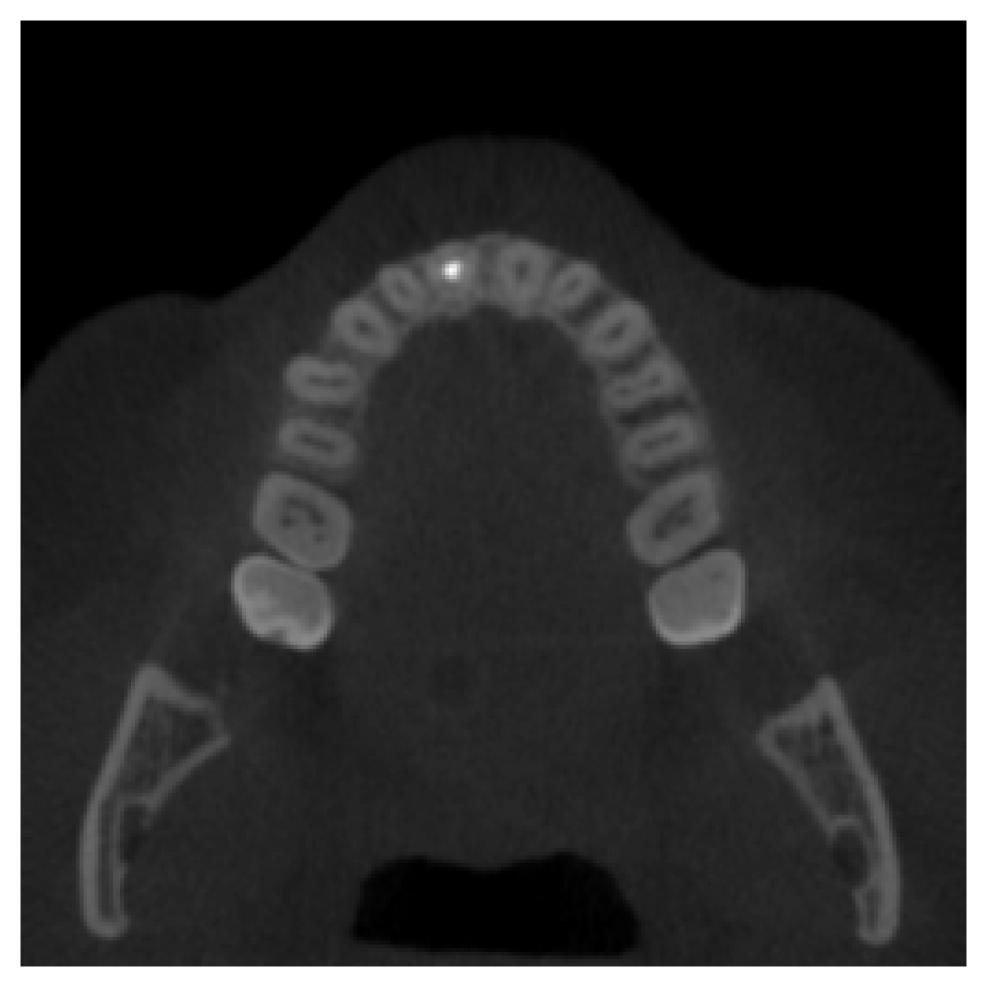

Full Dental Synthesis.

As a final experiment, we evaluate the model’s performance on generating a complete dentition in scans with no teeth present. This assesses the model’s ability to synthesize anatomically plausible full dental structures from the conditioning vector. Fig. 3 presents qualitative results comparing the generated samples to real scans with complete dentition. The visual comparison demonstrates a strong alignment between the real and synthetic inpainted regions. Quantitative evaluation supports this observation, with an average SSIM of 0.9123 and an average PSNR of 18.35 computed over the inpainted areas, despite the model not having seen the test samples during training.

Refer to caption

(a) Real Scan 1

(b) Synthetic Scan 1

(c) Real Scan 2

(d) Synthetic Scan 2

Figure 3: Qualitative comparison between generated CBCT scans and their corresponding real scans with complete dentition.